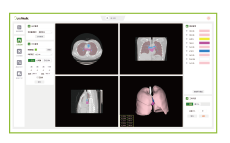

三維重修界面中,,,,,,可進行

一鍵全自動三維重修、交互重修

及測量標註等相關輔助性操作

剖析模塊界面中,,,,,,可進行

模子支解、模擬染色、標註測

量等輔助性操作

在融合顯示頁面中,,,,,,可與術中內窺鏡

手術畫面實時融合,,,,,,進行術中導航。。。。。。。。另外

還支持導入視頻顯示於主閱覽窗中,,,,,,並

把三維模子叠加在視頻中進行融合題示